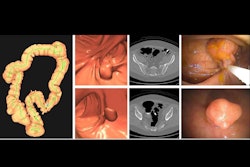

At long last, the U.S. Centers for Medicare and Medicaid Services (CMS) is now backing Medicare reimbursement for CT colonography (CTC) for colorectal cancer screening.

The CMS has included coverage of CTC in its proposed 2025 Hospital Outpatient Prospective Payment System (HOPPS) and 2025 Medicare Physician Fee Schedule (MPFS) proposed rules, which were published on July 10. The American College of Radiology (ACR), which has been lobbying the CMS to provide Medicare coverage for CTC for over 15 years, lauded the move, marking it as "a big step forward toward providing Medicare patients access to a minimally invasive colorectal cancer screening tool that can detect precancerous polyps and does not require anesthesia."

After considering recommendations as well as guidelines from appropriate organizations, the CMS wrote that it believes “CTC to be reasonable and necessary as CRC screening test, especially for patients and clinicians who seek a direct visualization procedure as a first step in CRC screening that is less invasive and less burdensome on the patient and healthcare system compared with Screening Colonoscopy. Our goal is that the patient and their clinician make the most appropriate choice in CRC screening, which includes considerations of the risks, burdens, and tradeoffs for each covered test or procedure. We expect that clinicians who order CTC for CRC Screening will educate their patients on risks and context of radiation exposure and potential extracolonic findings.”